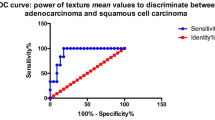

During a median follow-up of 36 months, tumor recurrence was found in 26 patients (22.6%). Multivariate analysis demonstrated that CE-T1 MPP and T2 kurtosis at SSF3–5, CE-T1 MPP at SSF6, and CE-T1 SD at unfiltered images were independent predictors of RFS (p < 0.05). Regarding the 2-year RFS for CE-T1 MPP and T2 kurtosis at SSF5, and CE-T1 MPP at SSF6, patients with > optimal cutoff values demonstrated significantly worse survival than those with ≤ optimal cutoff values (p < 0.05).